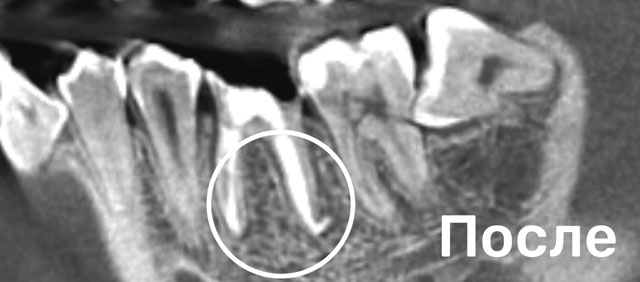

Перелечивали зуб с Марией Александровной после некачественного первичного лечения у другого врача. Образовалась киста + недобросовестный доктор оставил часть инструмента в канале. Очень понравилось то, Еще... что доставали часть забытого инструмента (и в общем все процедуры проводились) под микроскопом. Не было паники, что что-то повредится. Было всё абсолютно безболезненно. После всех процедур, через 2 месяца пришла на повторный снимок, киста практически ушла. Динамика хорошая. Безумно благодарна Марии Александровне за проделанную работу. За здоровыми и красивыми зубками – теперь только к ней!

После